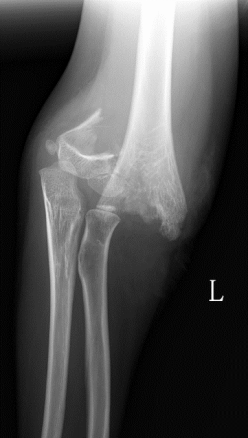

1、小红(化名):女、6岁、吊单杠时不慎摔伤致左肘部肿痛、畸形、活动受限2小时就诊我院。(下图为患儿术前X线片及CT检查)

此种类型的骨折称为肱骨髁上骨折,在完善相关辅助检查后予行麻醉下平乐郭氏手法正骨经皮钢针内固定治疗,术后患儿恢复良好,手术部位只有几个小针眼。(下图为患儿术后X线片)